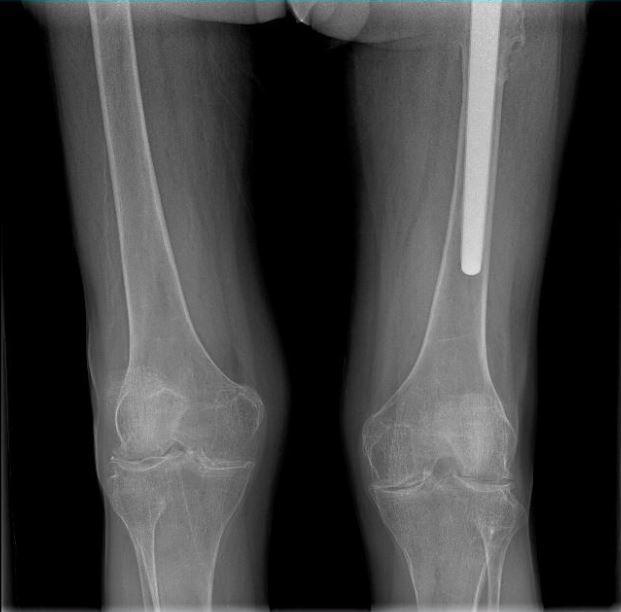

男 70岁

双侧股骨头置换术后

双侧股骨头置换术后复查

通过全景拼接图像可以清晰显示双下肢对比情况,为术后评估提供更多影像学资料。